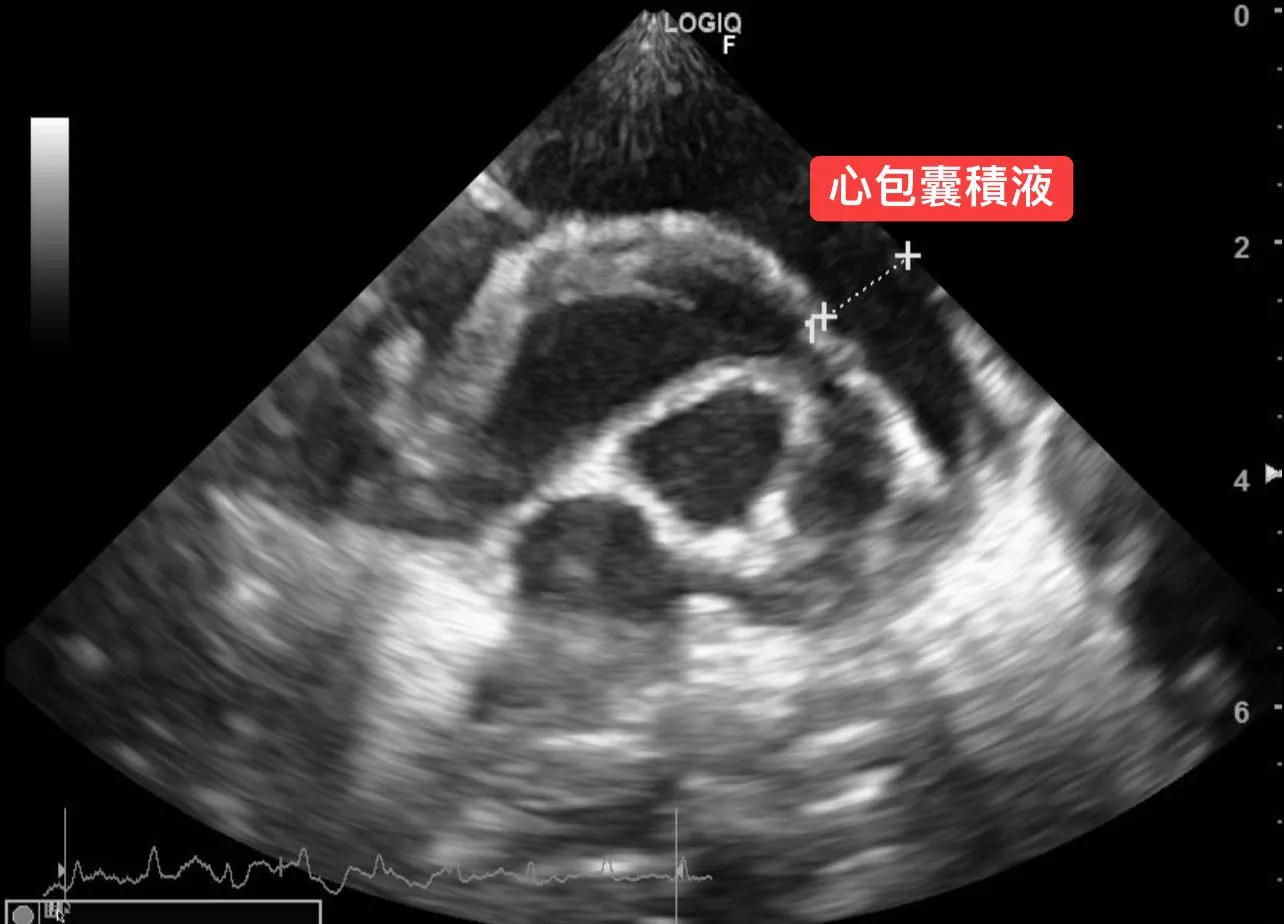

🫀第三步: 心臟超音波/心電圖檢查,診斷左右心房嚴重擴張、二尖瓣與三尖瓣逆流與肺高壓問題。

🫀第三步: 心臟超音波/心電圖檢查,診斷左右心房嚴重擴張、二尖瓣與三尖瓣逆流與肺高壓問題。